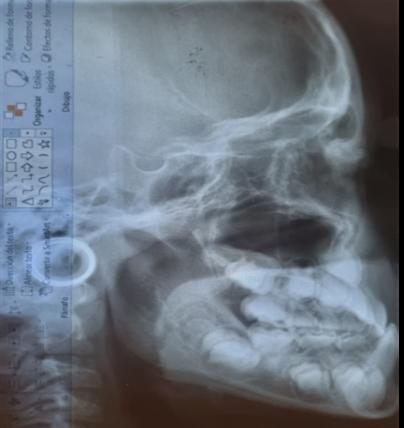

1. Carpio-Deheza G. Manual de instrucciones para la presentación de protocolos y monografías de diplomados, protocolos y tesis de espcialidad clínica/ quirúrgica, tesis de maestrías y doctorados en salud. Cochabamba: Universidad Mayor de San Simon, Facultad de Medicina Dr. Aurelio Melean, post grado UMSS; 2019.

2. Patrias K. Citing Medicine; The NLM Style Guide for Authors, Editors, and Publishers. [Online].: Bethesda (MD): National Library of Medicine (US); 2007 [cited 2022 marzo 29. Available from: https://www.ncbi.nlm.nih.gov/books/NBK7256/.